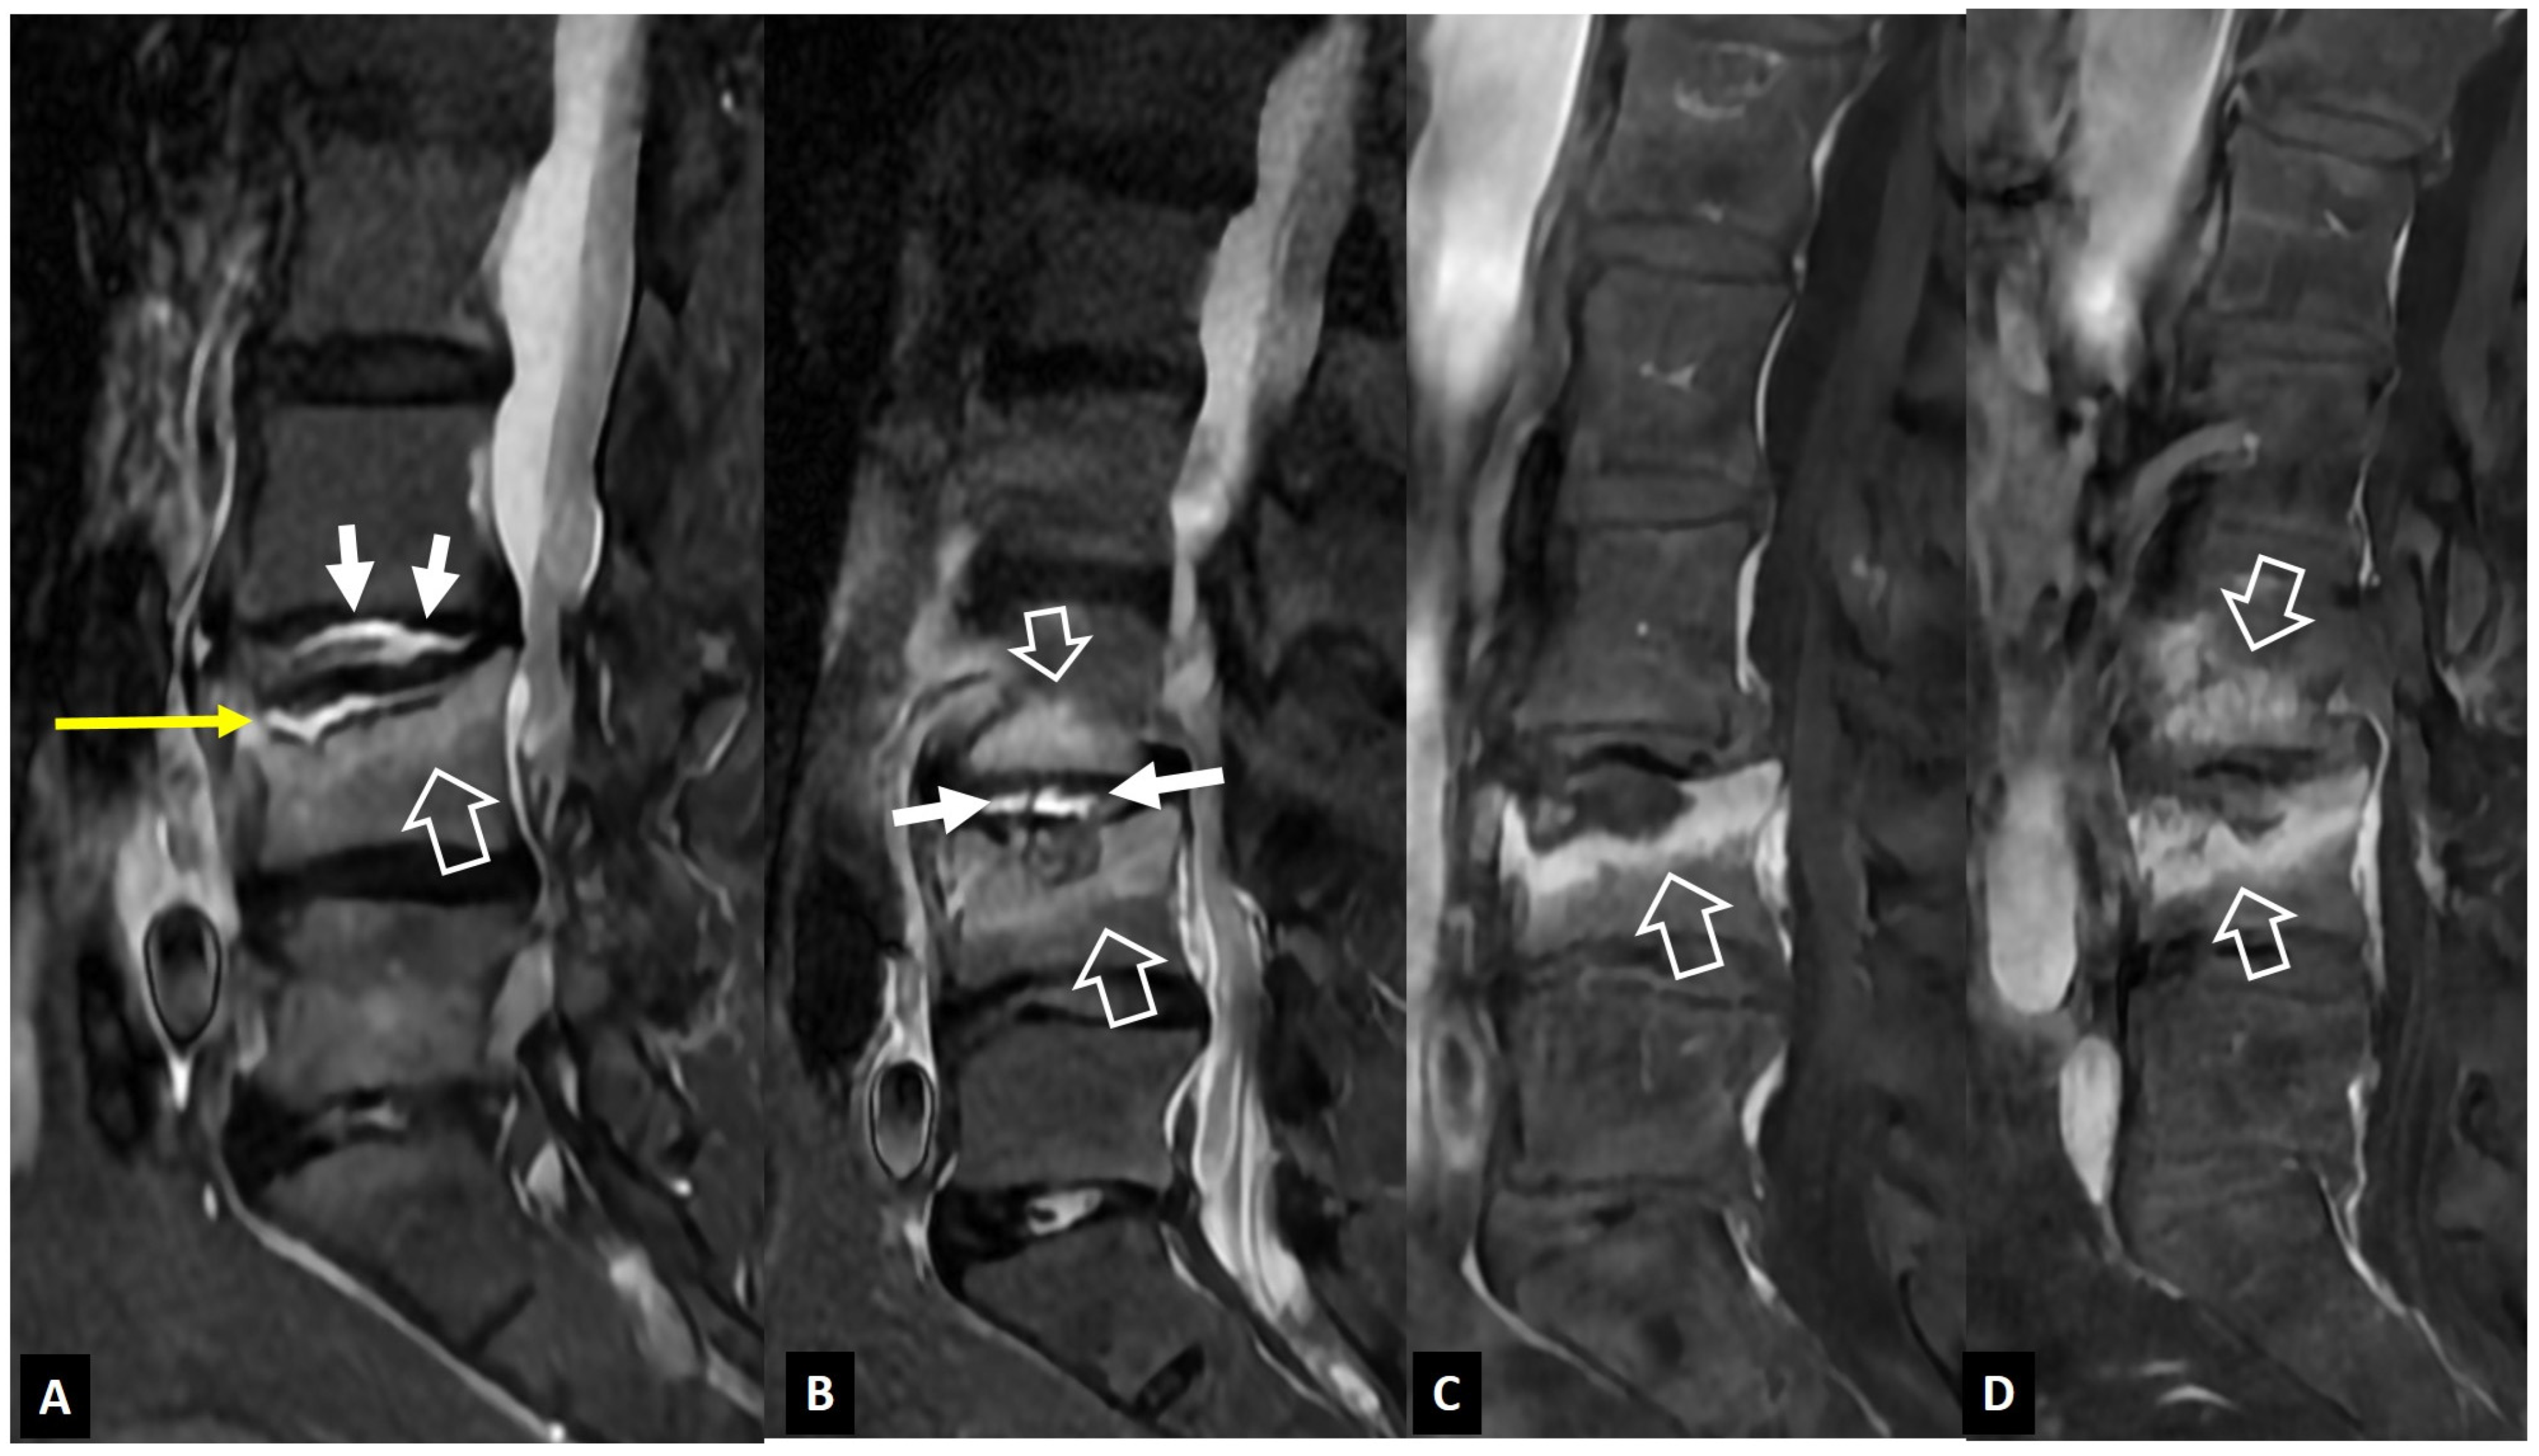

2.1.4. Destructive Spondyloarthropathy

- Kuntz, D.; Naveau, B.; Bardin, T.; Drueke, T.; Treves, R.; Dryll, A. Destructive spondylarthropathy in hemodialyzed patients. A new syndrome. Arthritis Rheum. 1984, 27, 369–375. [Google Scholar] [CrossRef]

- Theodorou, D.J.; Theodorou, S.J.; Resnick, D. Imaging in dialysis spondyloarthropathy. Semin. Dial. 2002, 15, 290–296. [Google Scholar] [CrossRef]